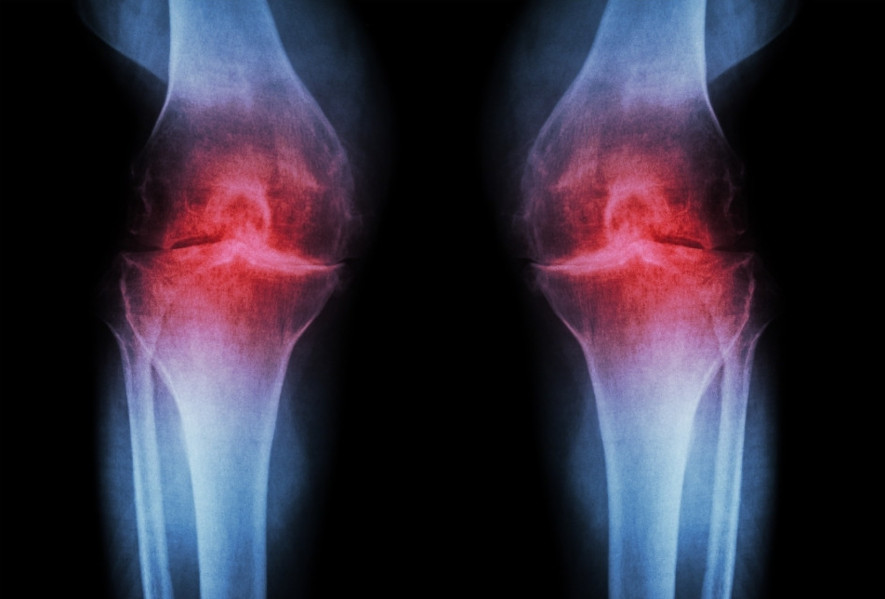

Notera de områden där brosket har brutits ner, vilket är karakteristiskt för knäartros.

Notera de områden där brosket har brutits ner, vilket är karakteristiskt för knäartros.

Knäartros, också känd som gonartros, är en diagnos som huvudsakligen orsakas av åldersrelaterad slitage på knäleden. Knäledsartros är den mest förekommande formen av artros, en sjukdom där brosket som skyddar och ger glidning i leden bryts ner över tid.

Brosk fungerar normalt som stötdämpare mellan benen i en led, och när det bryts ner kan det orsaka smärta, stelhet och svullnad. På längre sikt kan det till slut orsaka försämrad och smärtsam rörlighet i leden, vilket är vanligt hos personer med knäartros.